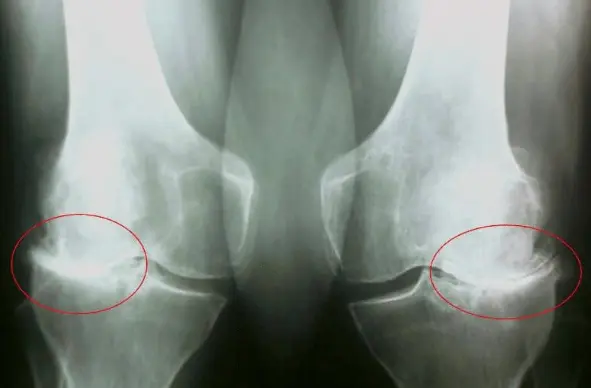

এই ছবিগুলো দেখো। সঠিক ছবিতে, জয়েন্টের জায়গা নেই, হাড়গুলো একে অপরের সাথে ঘষছে, যার ফলে তীব্র ব্যথা হচ্ছে। আর এই প্রক্রিয়া বন্ধ করা খুব কঠিন! কয়েক বছরের মধ্যে, ব্যক্তিটি অক্ষম হয়ে যাবে এবং নিজের যত্ন নিতে পারবে না।

এই সবই তরুণাস্থি টিস্যুকে নরম করে, জীর্ণ করে এবং পাতলা করে। প্রতিটি নতুন নড়াচড়ার সাথে, তরুণাস্থি জীর্ণ হয়ে যায় এবং বিকৃত হয়ে যায়, হাড়গুলি একে অপরের সাথে ঘষতে শুরু করে, যার ফলে অসহনীয় ব্যথা হয়।

রিউমাটয়েড আর্থ্রাইটিস এবং অস্টিওআর্থ্রাইটিস রোগ শুরু হওয়ার 3-5 বছরেরও কম সময়ের মধ্যে অক্ষমতা সৃষ্টি করতে পারে এবং আয়ু 15-20 বছর কমিয়ে দিতে পারে!